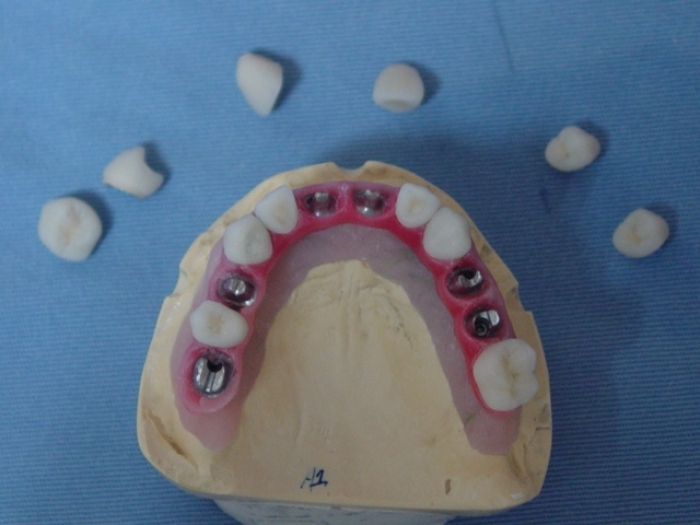

Prótese fixa de porcelana com dentes individuais

Imagens da prótese de porcelana com dentes individuais, ainda no laboratório